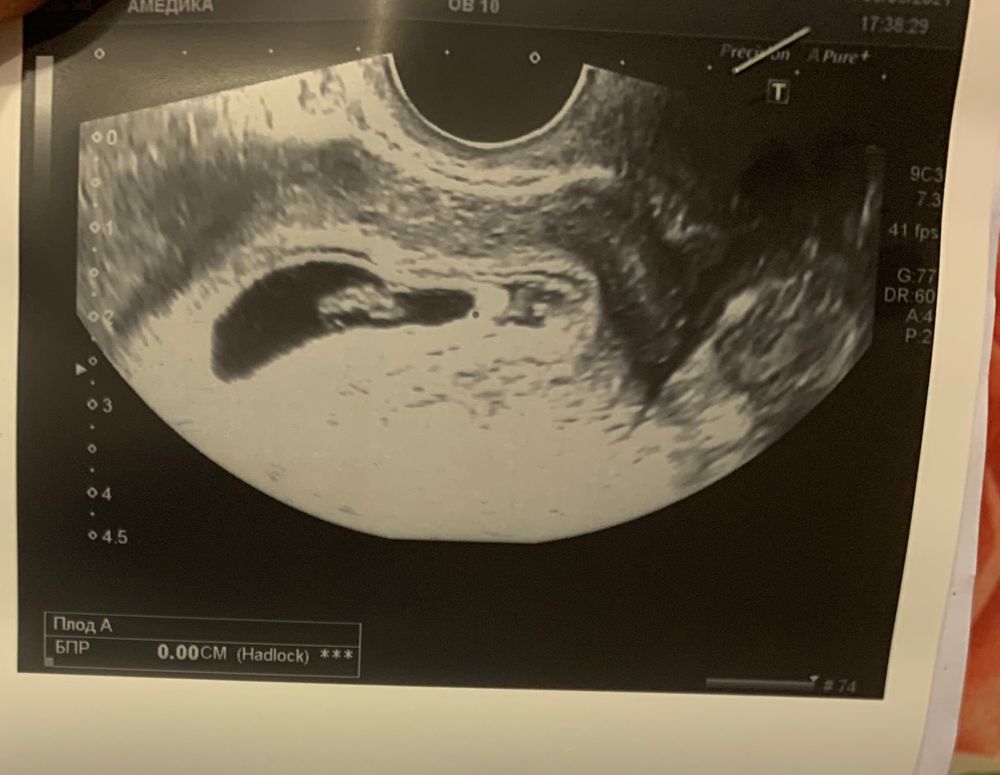

Метод Рамзи☺️

Наталия Мечтаю о Дочке, Изображение вот что врач на крайнем узи написала)

Вроде говорят если слева мальчик, а у вас справа , значит девочка ) но это не точно )

Валюшка Панкова, но тут зеркально ) потому что узи не по животу было, а трансвагинальное)

Валюшка Панкова, Доктор Рамзи установил, что в подавляющем большинстве случаев мужского пола плода хорион/будущая плацента располагается в правой стороне матки, а в случаях женского пола - в левой. Точность метода составляет более 97%, что сравнимо с точностью повсеместно используемых тестов на беременность. Вот) наверное мальчик 🙈

Анютка, я по своему смотрю узи . У меня девочка )) такое же расположение

по методу девочка, но почитайте даже тут на бебиблоге - это просто развлекушка, совпадает у 50 процентов.

Читала, что по методу Рамзи, если эмбрион прикрепился в матке слева - девочка, справа - мальчик. При вагинальном узи нужно отзеркалить. По вашей картинке малыш справа - отзеркаливаем - получается слева. Девочка. У меня с первым сыном сошлось - был справа, даже живот рос бугром с правой стороны. Сейчас кроха прикрепилась слева, предполагаю девочку.

Узи трансвагинально? Девочка💝